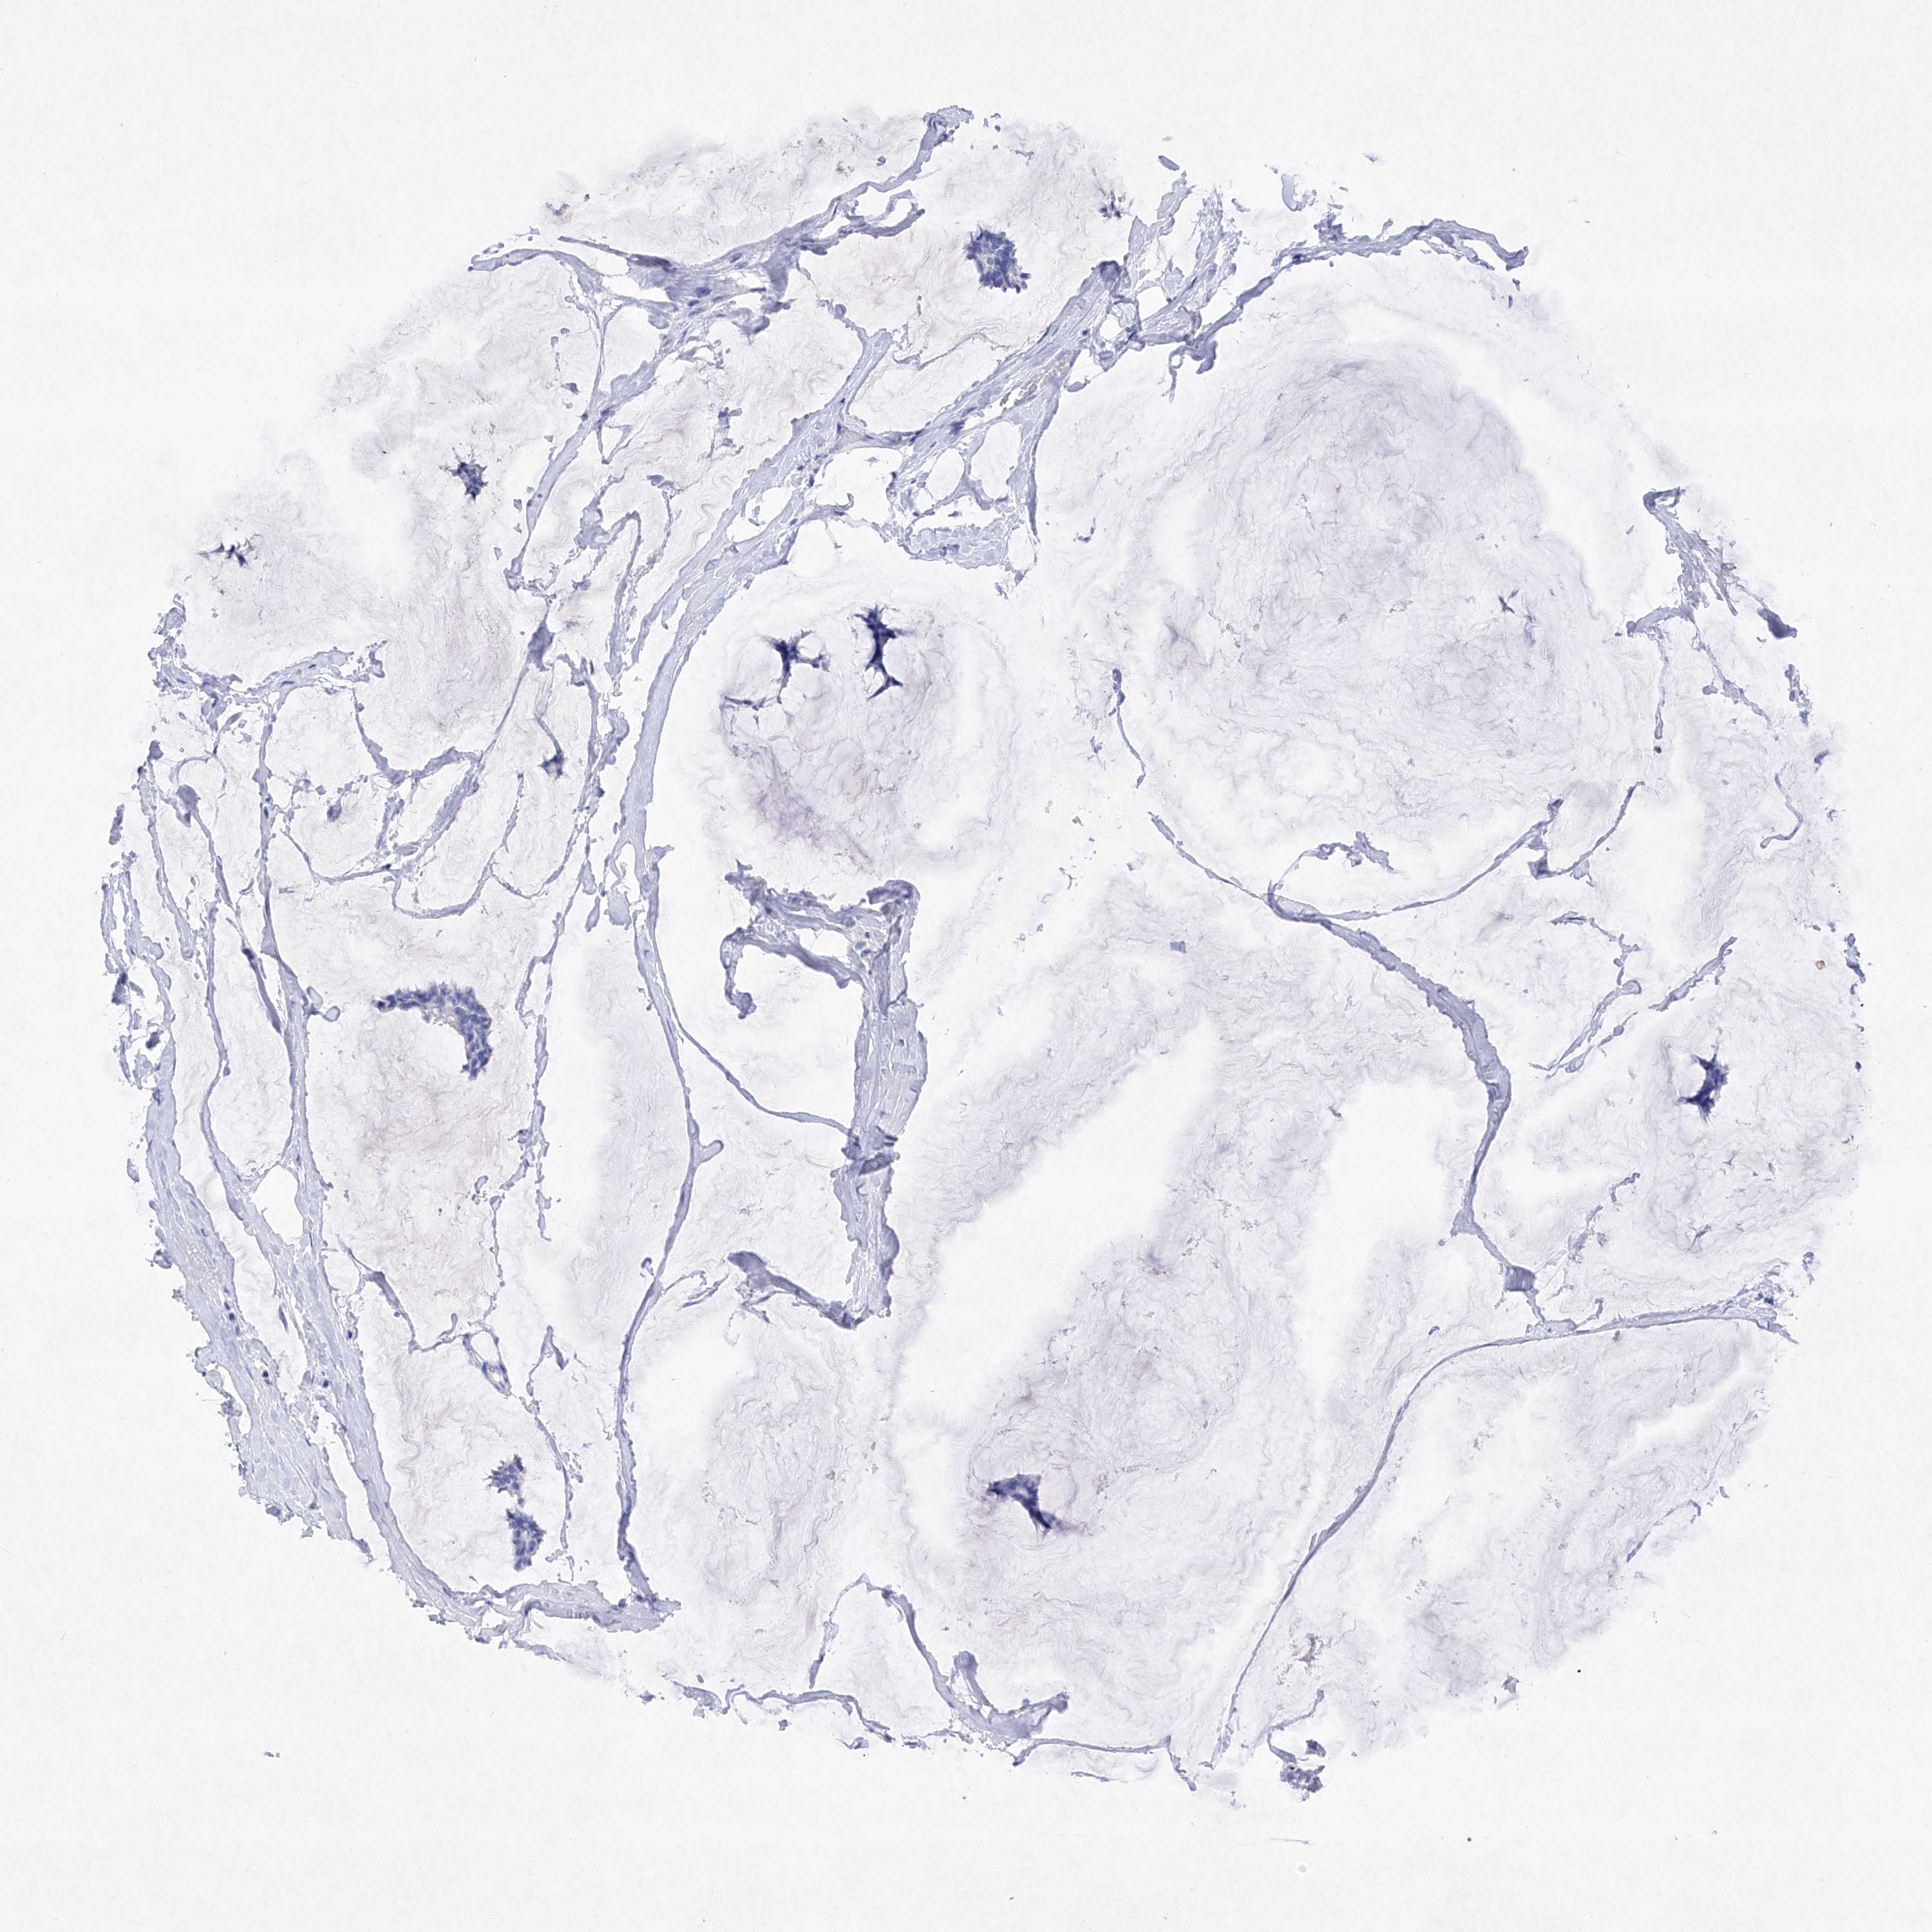

CANCER BREAST CANCER Show tissue menu

Breast cancer

Human cancer